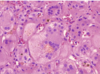

A neonate presents with high conjugated bilirubin and jaundice. Ultrasound rules out Biliary Atresia. What is the next most likely cause?

• Histological Appearance?

Next Most Likey = Neonatal Hepatitis

Histo:

• Multinucleated giant cells

• Lobular Dissarry, apoptosis, and necrosis

***See below